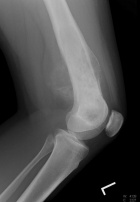

Patient is an 18 y/o female who presented c/o four month hx. of L. knee pain and swelling; she attended PT and x-rays revealed a lesion

PMH: unremarkable; PE: L. distal thigh w/ palpable warm mass; full PROM; NVI

Zoom image: Radiological image Radiological image.